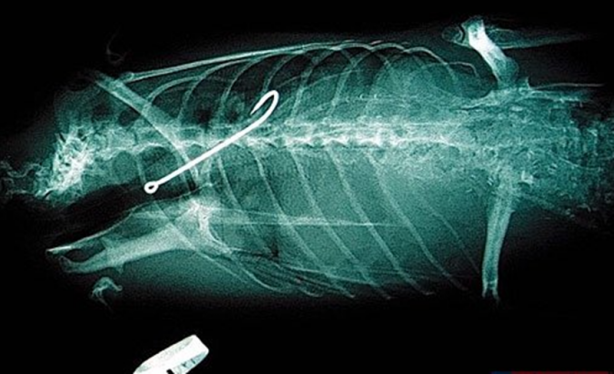

Çengelli iğne.